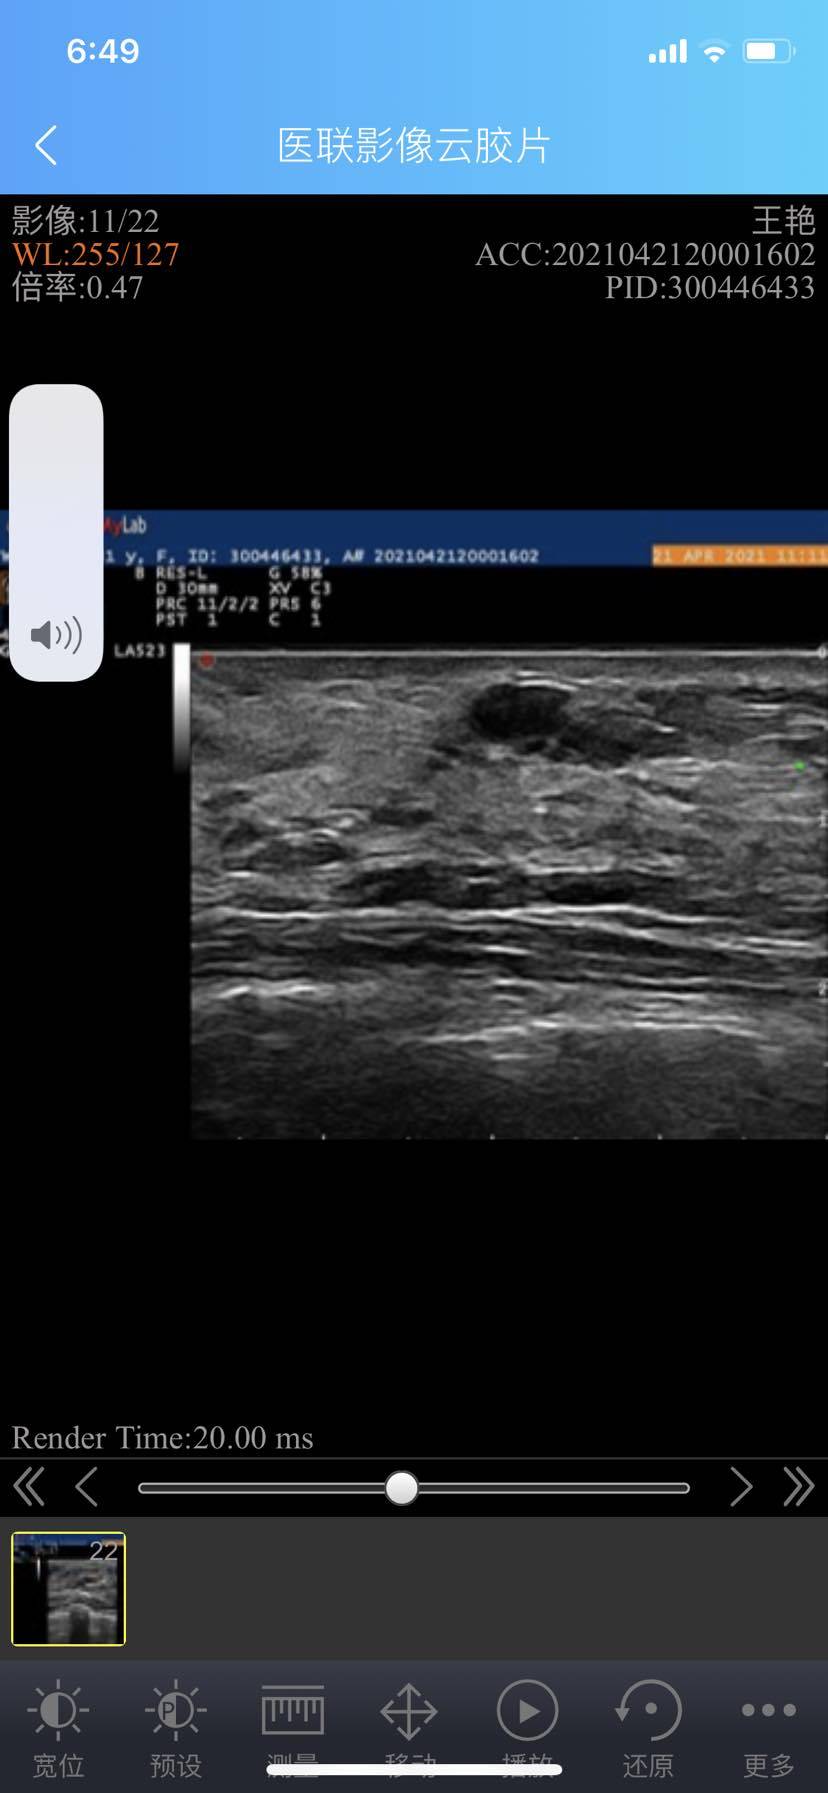

求助 结节不规则 很硬 活动性差 但是在瑞金和华山做b超判定三类

有没有人可以帮忙看看 我的结节很不规则形状 很硬